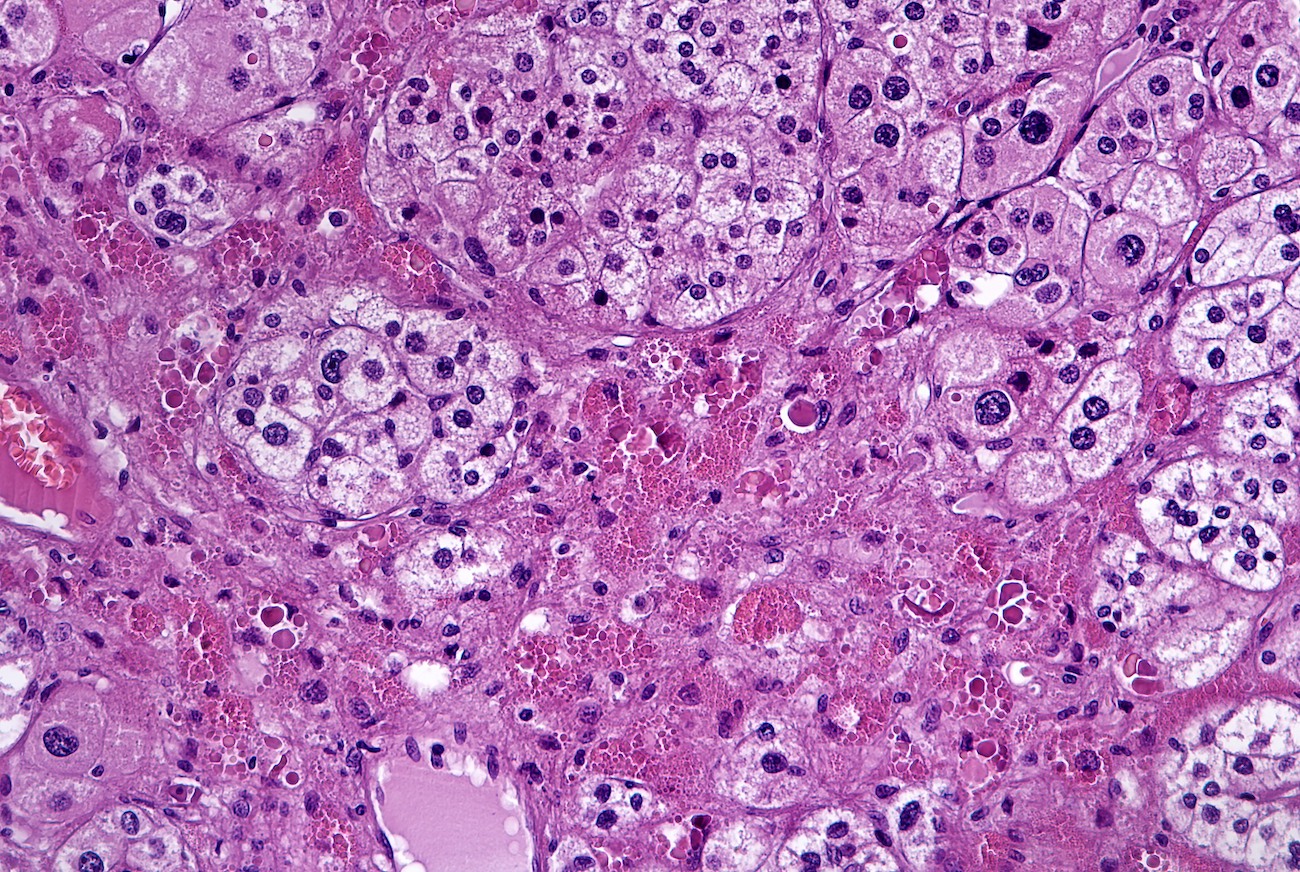

Microscopic (histologic) description

- In comparison to surrounding adrenal gland, adenoma cells are larger with different cytoplasm, increased variation in nuclear size

- Distinct cell borders, cells have abundant foamy cytoplasm reminiscent of zona fasciculata

- Balloon cells: clusters of cells with enlarged lipid-rich cytoplasm (seen in Cushing syndrome)

- Histologic variants: oncocytic, myxoid

Microscopic (histologic) images

Contributed by Xiaoyin "Sara" Jiang, M.D., Debra Zynger, M.D., @Andrew_Fltv on Twitter and @SueEPig on Twitter